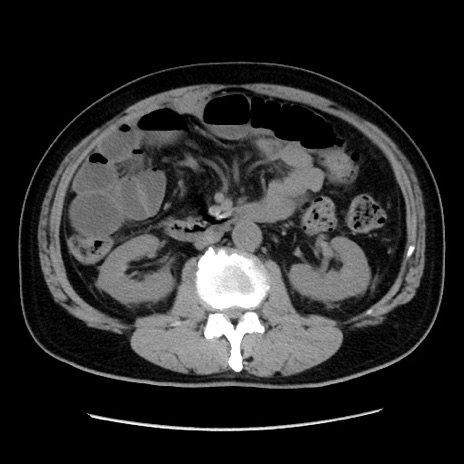

症例16(横断像)

【症例】 70歳代男性

【主訴】 腹痛、嘔吐

【現病歴】 約1ヶ月前より間欠的に腹痛と嘔吐あり、当院消化器内科を受診したところCTで多発する肝臓のLDAを指摘され、精査中であった。以降は消化器症状は安定していたが、2日前より嘔気と腹痛があり、同日より排便・排ガスが消失した。改善認めず、 本日、救急外来を受診した。

【身体所見】意識清明・会話良好、BT 36.3℃、BP 127/80mmHg、 P 80bpm、腹部:膨満あり、平坦・軟、上腹部正中および下腹部正中に圧痛あり、反跳痛なし、筋性防御なし。

【データ】WBC 7200、CRP 0.77